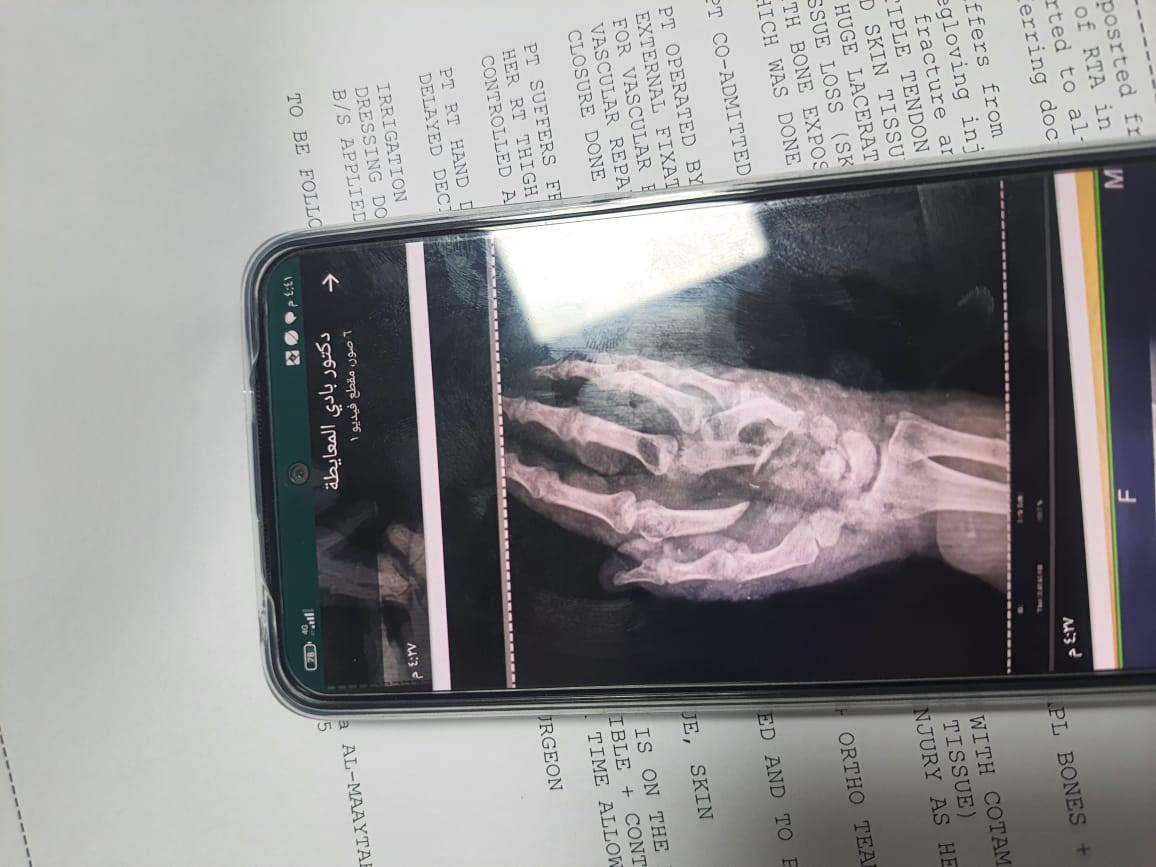

وتعاني هناء من إصابة حرجة في رجلها بالإضافة إلى حصول مضاعفات والتهاب بها بالإضافة إلى ذراعها، الأمر الذي دفع الأطباء للحديث حول امكانية "بتر" ساقها وذراعها حتى لا تزداد حالتها الصحية سوءاً.

وناشدت كندا الجهات المسؤولة بمساعدة شقيقتها ونقلها إلى مستشفى الخدمات الطبية لتلقي العلاج المكلف، والعمل على انقاذها من "بتر" ساقها وذراعها، وإعادة الحياة والفرحة إلى قلبها من جديد.